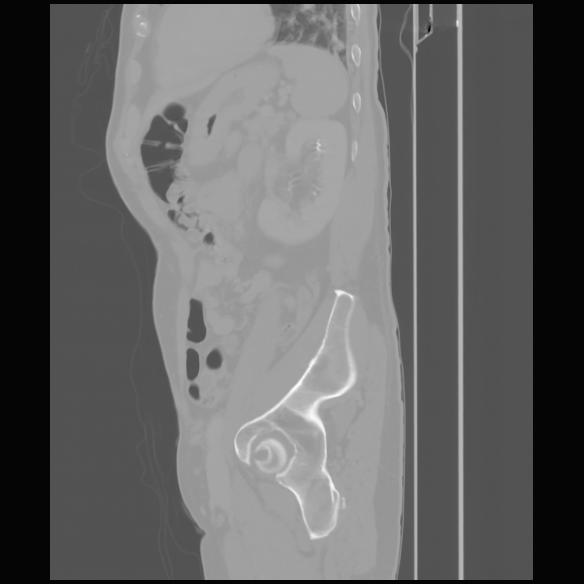

7 CUERPO,CE,Sagittal,3.000,CUERPO,Sagittal,